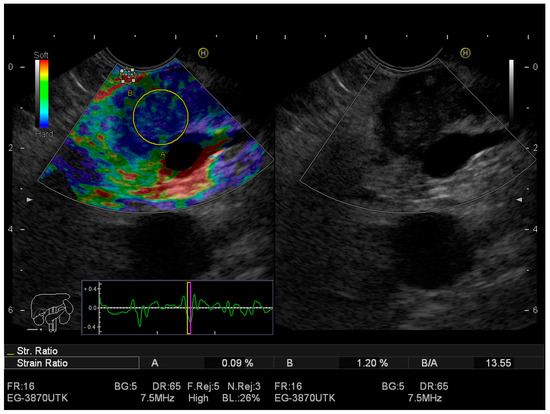

2.1. Real-Time Elastography EUS (RTE-EUS)

| Zhang B et al. [62] | 1044 | 95% | 67% | 42.28% | EUS elastography |

| Lu Y et al. [63] | 1544 lesions | 97% | 67% | - | Qualitative methods |

| Lu Y et al. [63] | 1544 lesions | 97% | 67% | - | Strain histograms |

| Lu Y et al. [63] | 1544 lesions | 98% | 62% | - | Strain ratio |